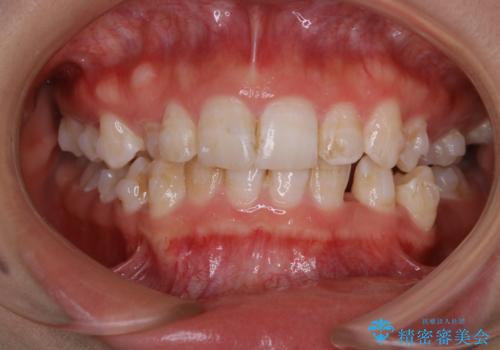

全体的な治療の開始前に着色取り

担当医 歯科衛生士